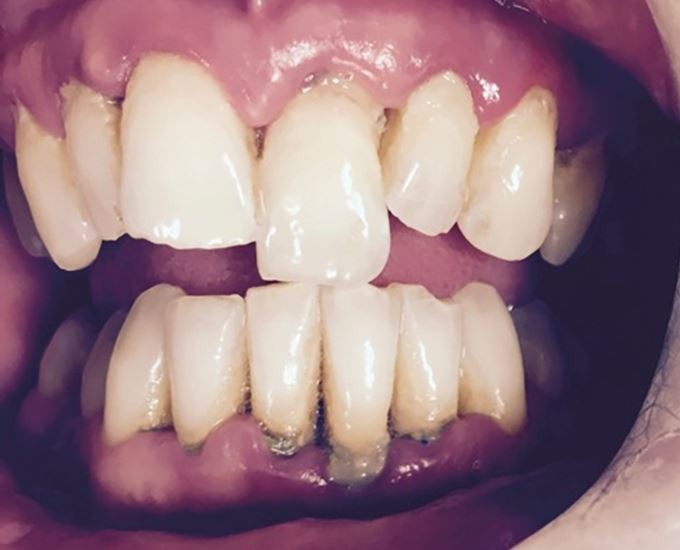

After replantation, teeth need dental splinting and ideally in a surgery, but possibly on-site if facilities allow. Common splinting techniques are described from composite and orthodontic wire (<0.4 mm diameter) to novel approaches using fishing line or suturing across teeth.49 Splints should be easy to apply and remove, not interfere with occlusion, and allow access for endodontic treatment and oral hygiene measures (Fig. 19).

An orthodontic wire and composite dental trauma splint